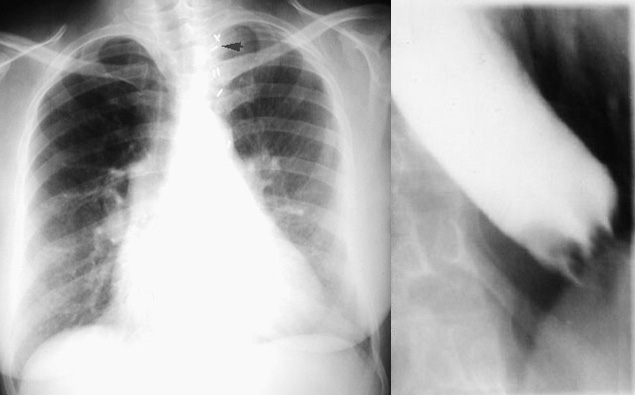

There can be significant interstitial disease with a normal CXR as seen in this patient who had marked diffusion defect. Sympathectomy clips (arrowhead) for Raynaud's phenomenon.

Dilated esophagus on barium swallow.